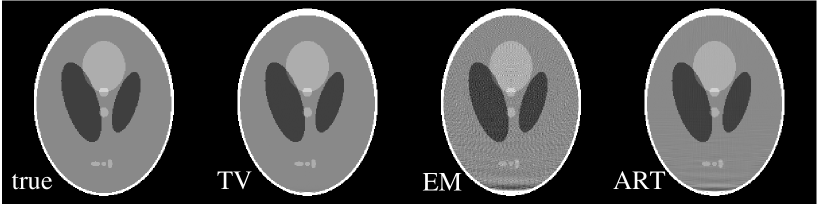

The first case is a reconstruction problem from few-view projections in fan-beam CT. Using the Shepp-Logan phantom shown in Fig. 4A, we generated projection data at 20 view angles specified by:

| (19) |

Though sparse, the angles cover 360∘ about the object. The shift in the second half of the angular measurements helps to reduce redundancy in the scanned data. The total number of measurement rays is , but only 8,236 of these projection elements are non-zero. This number is larger than the twice the support of the gradient image, but it is well below the support of the Shepp-Logan phantom itself. In addition, the angular direction is severely undersampled.

From the projection data generated at the 20 views, we reconstructed images, as shown in row one of Fig. 4, by use of the TV, EM, and ART algorithms. The number of iterations for each algorithm was 200. For a quantitative comparison, we also compare the image profiles along the central lines of the images in the horizontal and vertical directions. The results in Fig. 4 indicate that the TV reconstruction is visually indistinguishable from the true image, suggesting that the system matrix corresponding to sparse fan-beam data may have the ERP even though the column vectors of the system matrix do not form an ortho-normal basis. The EM and ART results show considerable artifacts.